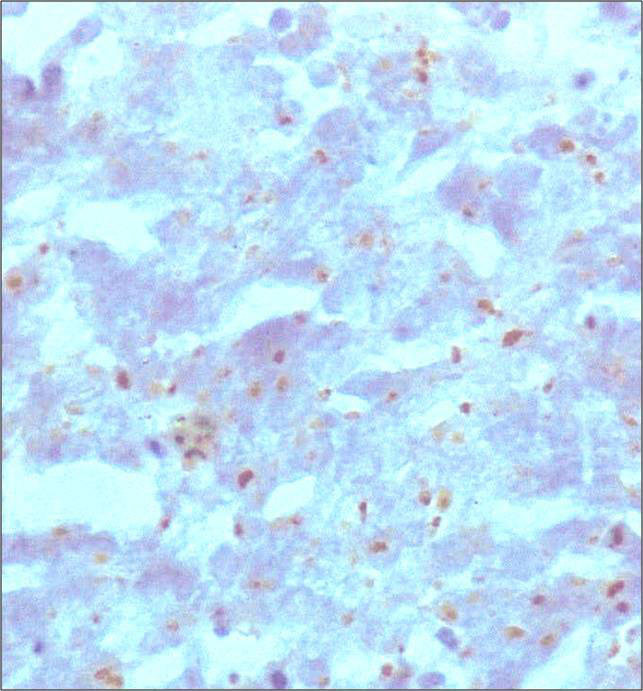

Immunohistochemical staining with cytokeratin 20 demonstrates a paranuclear dot pattern (see figure below), which is characteristic. They also express other neuroendocrine markers such as chromogranin, synaptophysin and CD56. In contrast to small cell carcinomas of pulmonary origin, they are negative for cytokeratin 7 and TTF-1.

Merkel cell carcinoma stained with CK 20